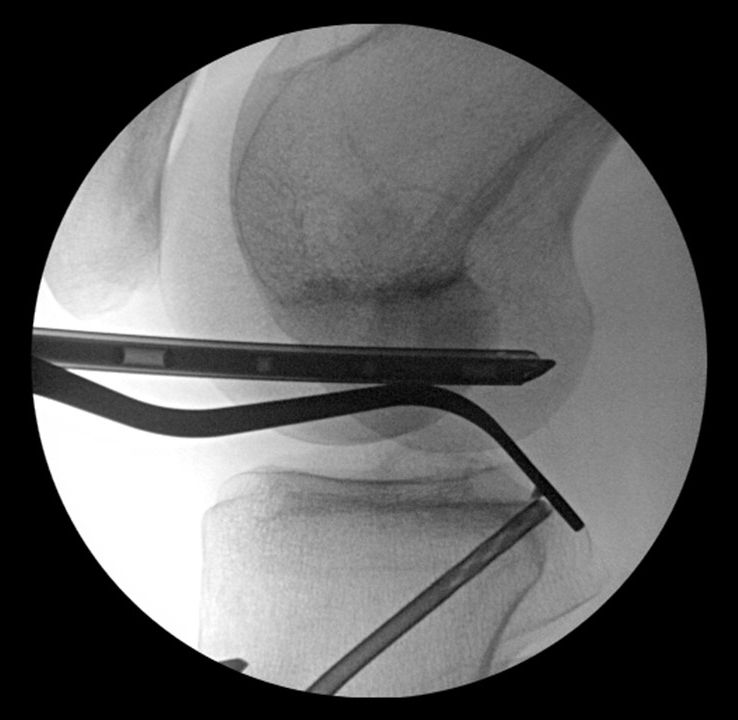

Now the retrodrill guide system with the 12mm cutter from anterior is brought in and the position of the cutter is controlled by lateral view under fluoroscopy (Fig 19).

Fig 19 - Arthroscopic view – 70° scope and fluoroscopic control

Then a 10mm socket on the posterior tibia at the level of the previous physis line is drilled and the retrodrill while leaving the cannulated pin is withdrawn (Fig 20). A fiber stick suture is inserted in the cannulated pin and temporarily pulled out posteromedial. The femoral tunnel in size congruent to the tendon part of the graft is drilled with the retrodrill system. A tiger stick suture is inserted femoral from outside-in and catched together with the previous tibial inserted fiber stick (Fig 21) intraarticular and pulled out through the anteromedial portal.

Fig 20 and 21 - Drilling the tibial 12 x 10 mm socket at previous physis line and visualization of posterior socket from posteromedial